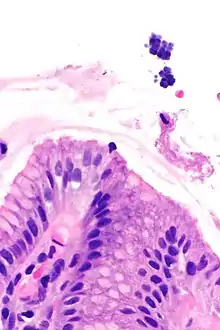

Gastric mucosa and Sarcina on upper right. H&E stain.

Sarcina is a genus of Gram-positive cocci bacteria in the family Clostridiaceae.[2][3][4] A synthesizer of microbial cellulose,[5] various members of the genus are human flora and may be found in the skin [6] and large intestine.[7] The genus takes its name from the Latin word "sarcina," meaning pack or bundle, after the cuboidal (2x2x2) cellular associations they form during division along three planes.[8]

The genus's type species is Sarcina ventriculi, a variety found on the surface of cereal seeds, in soil, mud, and in the stomachs of humans, rabbits, and guinea pigs.[9]